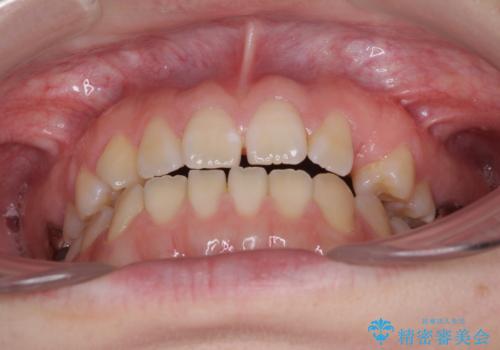

- 前歯の開咬と、受け口による咬み合わせの悪さを気にして来院された患者様です。

左上は後続永久歯の欠損によりスペースがあり、矯正治療と並行してインプラントあるいはブリッジによる補綴治療が必要な状況でした。

上顎歯列が狭窄していたため、急速拡大装置により上顎骨を側方に拡大し、その後インビザラインにて矯正治療を行うこととしました。

矯正治療と並行してインプラントによる補綴治療を行うこととしました。